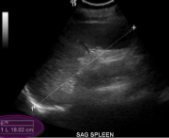

Sag Spleen

Left side coronal

Sag Spleen measurement- tip to diaphgram

perp measurement

Trv Spleen

Trv Spleen measurement

width

Sag Spleen (1.5-2.0cm)